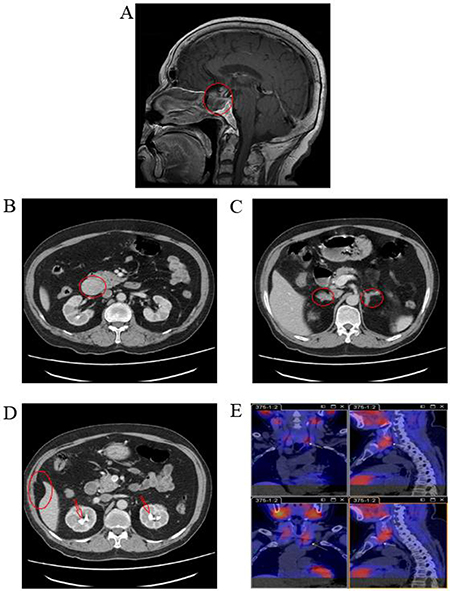

The proband (II-3), a male born in December 1945, visited Xiangya Hospital in August 2010 for dizziness. Magnetic resonance imaging (MRI) revealed a 2.0 × 2.5 × 2.5 cm pituitary tumor (Figure 1A) that was presumed to be a functional pituitary adenoma due to the high serum prolactin level (Table 1). The patient refused surgical treatment. Therefore, 10 mg/day of bromocriptine was administered, and regular follow-up visits were instituted. Subsequent examinations indicated that the pituitary adenoma had been controlled. In March 2014, the patient revisited Xiangya Hospital for epigastric pain, sicchasia, and vomiting. Abdominal computed tomography (CT) revealed a 4 × 3 cm solid mass localized in the pancreatic head, bilateral renal stones, bilateral adrenal nodules, and abdominal lipoma (Figure 1). Cervical ultrasonography revealed a left 8 × 5 mm and a right 9 × 5 mm auxetic parathyroid nodule. Barium meal examination revealed chronic non-atrophic gastritis and multiple polyps of the duodenal bulb (data not shown). The pancreatic tumor was surgically resected and histologically diagnosed as a pancreatic neuroendocrine tumor (data not shown). The blood biochemistry prolactin and parathyroid levels were outside the normal range (Table 1). A patient with 2 or more MEN1-associated tumors should be diagnosed with MEN1 according to the clinical diagnostic criteria [7]. In August 2016, the patient returned to Xiangya Hospital as the parathyroid nodule was enlarging progressively. Single-Photon Emission Computed Tomography (SPECT) revealed multiple nodules behind the thyroid (Figure 1). The parathyroid tumors were resected and diagnosis of adenoma with lymphatic metastasis was confirmed by pathology (data not shown).

Figure 1: Medical imaging of the proband, II-3, in the MEN1 syndrome family. (A) MRI scans revealed a 2.0 × 2.5 × 2.5 cm pituitary tumor in the proband; (B, C, and D) Abdominal CT revealed a solid mass in the pancreatic head, bilateral adrenal nodules, bilateral renal stones, and abdominal lipoma in the proband; (E) SPECT revealed multiple nodules behind thyroid in the proband. MRI, magnetic resonance imaging; CT, computed tomography; SPECT, single photon emission computed tomography.